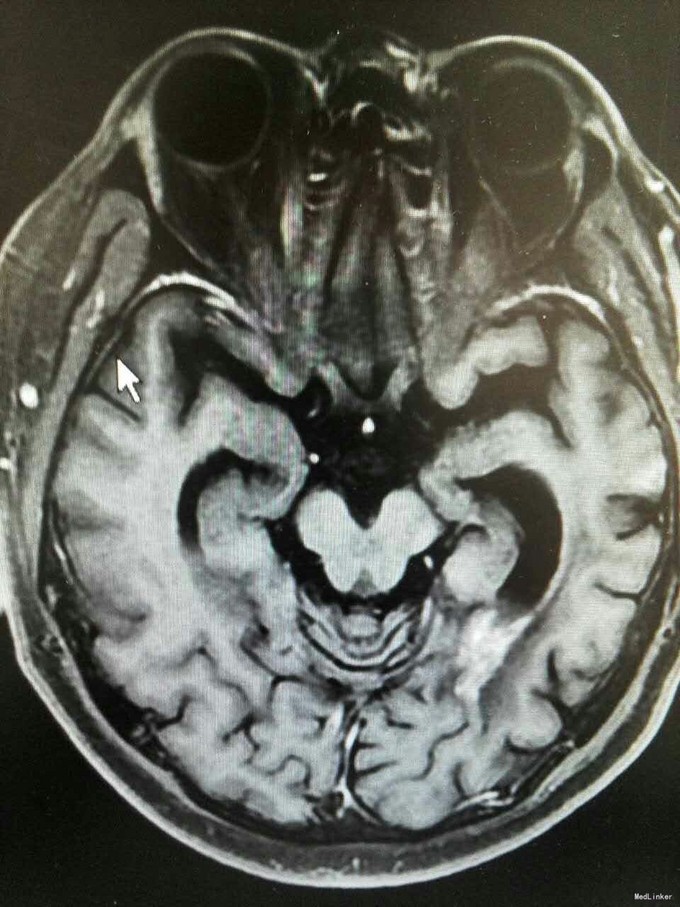

患者姜磊,男,49岁,主因"发作性视野缺损、失认8年余"于2015-11-20再次入我院,患者缘于8年前无诱因出现发作性视野缺损,伴阅读能力、理解力、认知能力下降,每次发作症状持续约3-5分钟左右,可自行缓解,无意识丧失、视物旋转、言语不利,无肢体活动障碍、大小便失禁。入院复查头颅MRI平扫+增强示:原左侧小脑幕、颞叶炎症治疗后,与2014-09-10日片比,病灶较前增多、增大。8年来间断在我院以:颅内非特异性炎症、症状性癫痫、高血压病 住院治疗,患者症状时轻时重,病灶反反复复,激素治疗有效。 病史汇报: 于2007年12月12日因"发作性视野缺损、失认1月"入我院,查头颅MRI示:左侧幕上颞底片状异常信号,并局部强化,考虑:炎症可能,肿瘤不排除;行腰穿检查,颅压120mmH2O ,外观清亮,脑脊液常规、生化均正常。脑电图轻度异常。给予复方磺胺甲恶唑片、青霉素、阿昔洛韦、激素(醋酸泼尼松片)等治疗。 2008年1月8日复查头颅MRI示:原左侧幕上颞底炎性病变范围缩小,综合考虑原颅内病变为炎性病变。于2008年1月19日出院,共住院37天。出院后仍间断出现发作性视野缺损症状。于2008-5-6复查头颅MRI示原左颞叶病变范围有缩小,支持局灶性脑炎的诊断。于2008.5.22~6.12予青霉素480万单位2/日巩固治疗30天。鉴于反复出现发作性视野缺损症状,于2008.6.5诊断性服用卡马西平片后上述症状未再发作,于是坚持服用卡马西平片(0.1g3/日)1年,服药期间未再出现发作性视野缺损症状。 于2012-05-29再次因"发作性双眼右侧视野缺失、闪烁感6天"入院,查头颅MRI示:原左侧幕上颞叶病变治疗后改变,考虑为炎性病变,结核可能。行腰穿示压力125mmH2O,脑脊液常规:颜色:无色,透明度:水样透明,潘氏试验:阴性,红细胞计数:80×106/L,白细胞计数:0x106/L,单个核细胞75%,多核细胞20%,脑脊液生化:蛋白508mg/L,葡萄糖3.3mmol/L,氯化物115.4mmol/L。脑电图印象:基本节律为低-中幅的α波, 频率调幅调节欠佳,分布可,左侧枕区波幅可见较右侧枕区减低。头前区可见少量低幅θ波及β波。深呼吸中见4-5hz慢波增多,有时呈短至中程节律,头前区为著,左侧偏胜。深呼吸后恢复好。睁闭眼试验:半抑制。闪光刺激:未见异常。脑电地形图:以α功率为主,可见θ功率。结论:轻度弥慢性异常脑电图及地形图;给予改善循环、营养神经、活血化瘀、脱水、激素等对症治疗。住院期间未再出现上述发作。 于2013-1-5再次因"发作性双眼右侧视野缺失、闪烁感1周。"入院,行头颅MRI示:左侧颞叶病变治疗后改变,与2012-07-24日片比,左侧小脑幕病变较前增大,左侧颞叶出现新病灶。给予改善循环、营养神经、活血化瘀、抗癫痫、抗感染(青霉素)、激素冲击(甲强龙)治疗后病情好转,于2013-4-15复查头颅MRI病灶再次缩小。患者出院后上述症状仍偶有发作。 于2014-5-12、2014-9-10复查头颅MRI病灶有增大趋势,再次给予抗炎(激素)等对症治疗后,于2014-11-24再次复查头颅MRI示:原左侧小脑幕、颞叶病变治疗后改变,与2014-09-10日片比较,较前明显缩小,水肿较前明显减轻。